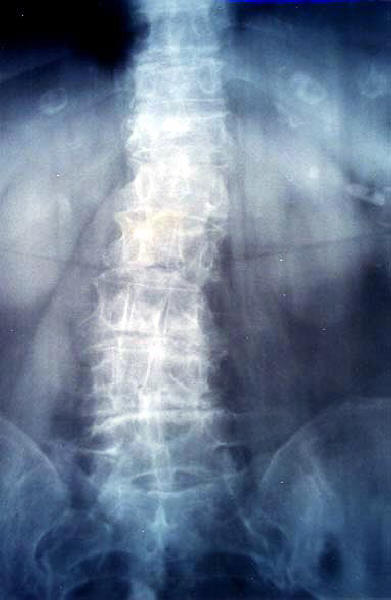

Artrosis lumbar con pinzamiento.

Artrosis lumbar